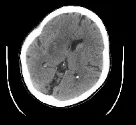

患者在发病80分钟时完成CT平扫,显示右侧颈动脉及大脑中动脉(MCA)M1段、M2段高密度征,提示血栓非常长;ASPECTS评分10分。

术后即刻CT,发现造影剂部分外渗。

24小时复扫CT,造影剂外渗完全消失。